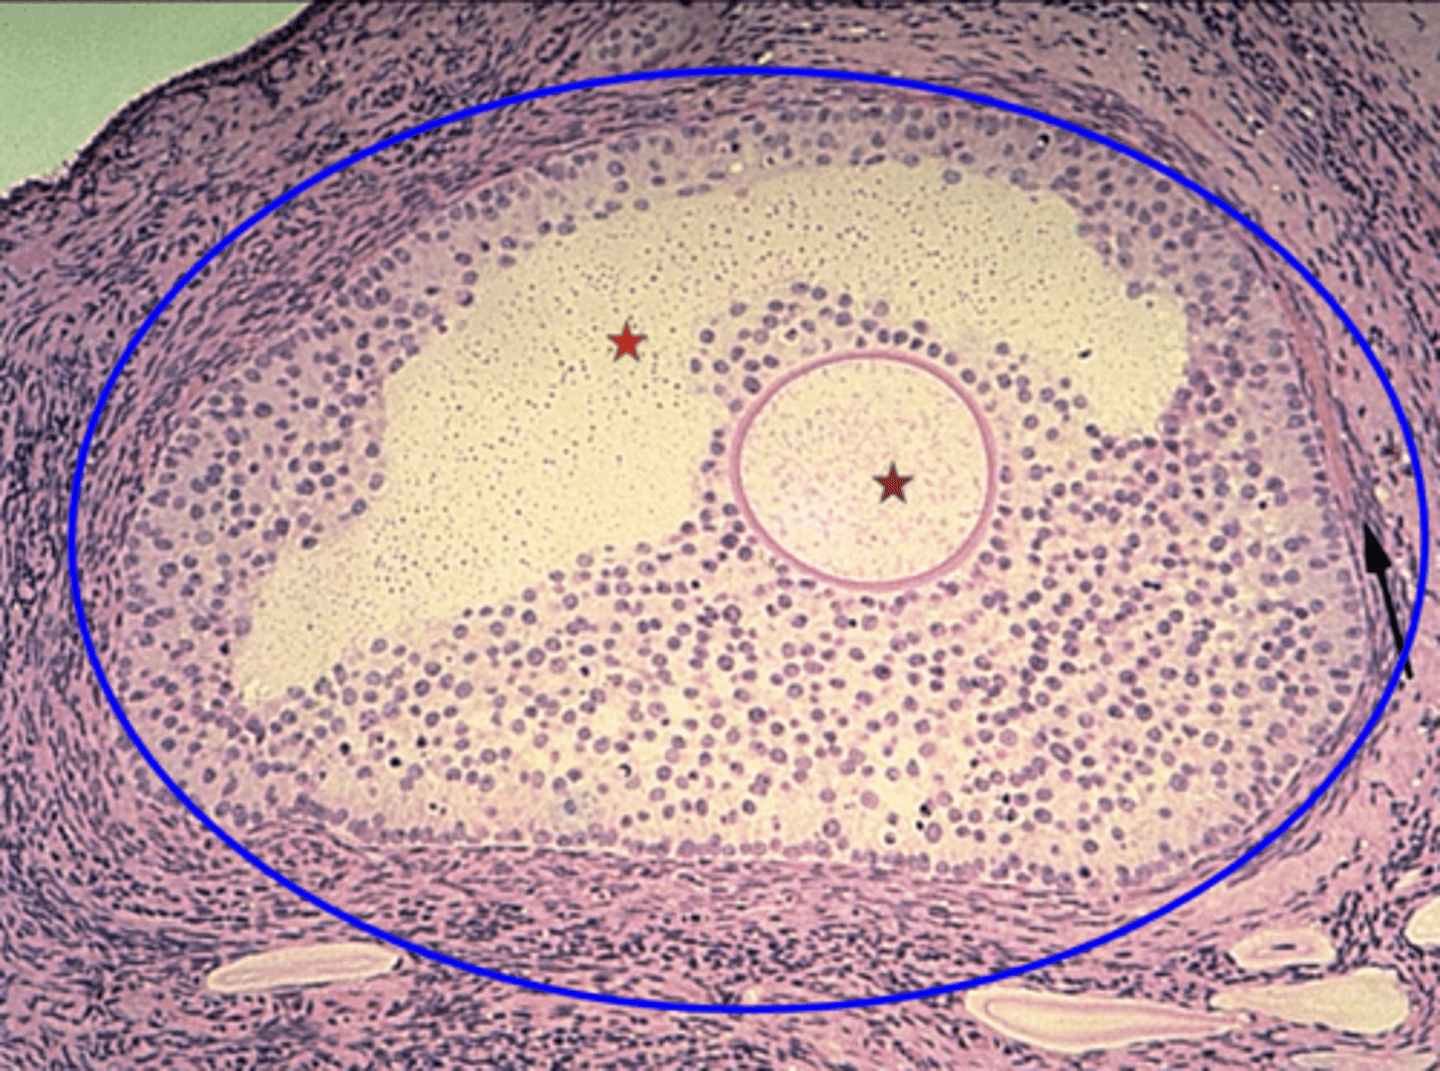

Germinal epithelium

What is the black arrow?

Tunica albuginea

What is the red arrow?

Primordial follicles

What is the green circle?

Multilaminar primary follicle

What is the blue outline?

Primary oocyte

What is the red star?